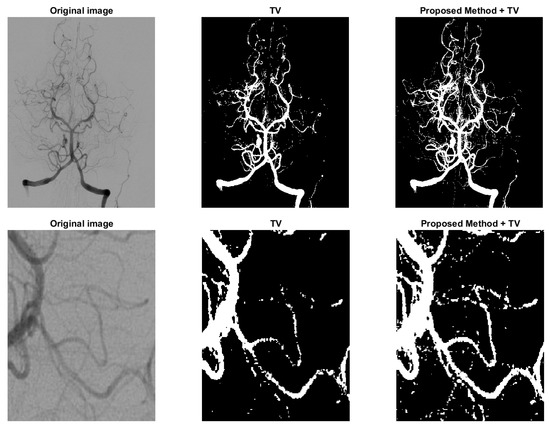

4.2.3. Unsupervised Model